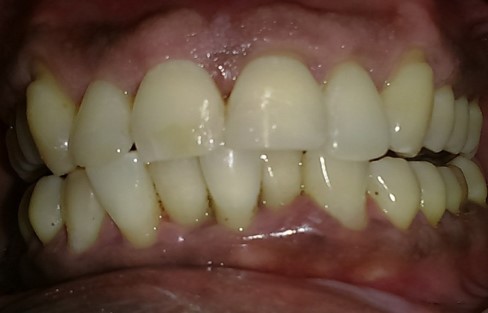

PRE - OP POST - OP